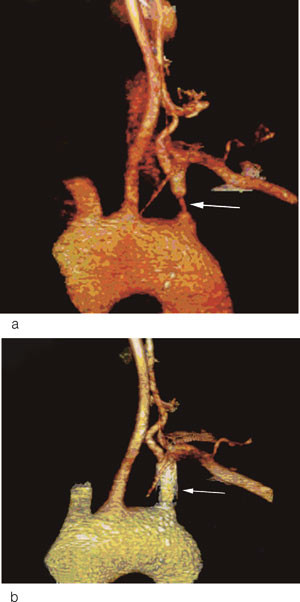

En 39 år gammel kvinne søkte lege etter flere episoder med svimmelhet og bilateral synssløring. Symptomene var spesielt relatert til brå hodebevegelser og nakkeekstensjon, blant annet hadde hun synkopert i forbindelse med opphenging av klær. Det ble målt en systolisk blodtrykksforskjell på 25 mm Hg mellom høyre og venstre arm. CT-angiografi og tripleks ultralyd av halskar viste en proksimal høygradig stenose i venstre a. subclavia samt komplett retrograd blodstrøm (grad 3) i ipsilateral a. vertebralis (fig 2a). Pasientens symptomer ble knyttet til subclavian steal-hemodynamikk med intermitterende iskemi av hjernestammen og synscortex. Hun ble endovaskulært behandlet med stentinnleggelse i venstre a. subclavia. Ved CT-angiografi tre måneder etter behandlingen var a. subclavia åpen og pasienten hadde ikke lenger symptomer (fig 2b).